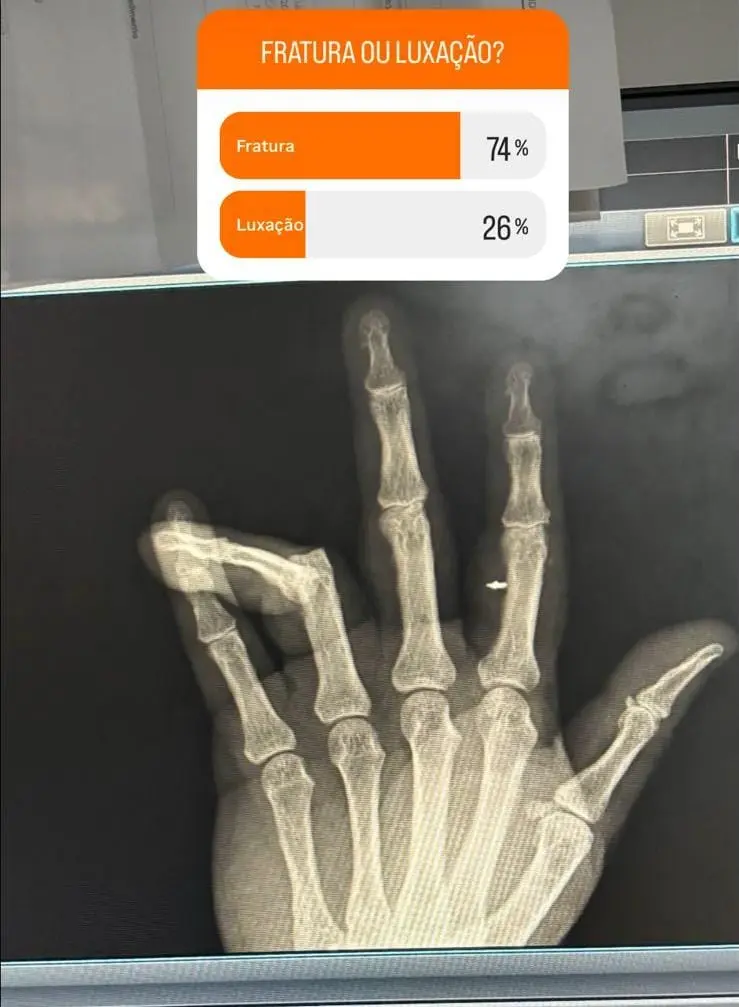

Vereador Alberci fez enquente nos stories sobre sua fratura/Foto: Reprodução

Após a confusão, o vereador Albecir foi levado ao hospital. Ele compartilhou em suas redes sociais uma foto do raio-X da mão e fez uma enquete para seus seguidores decidirem se era luxação ou fratura.